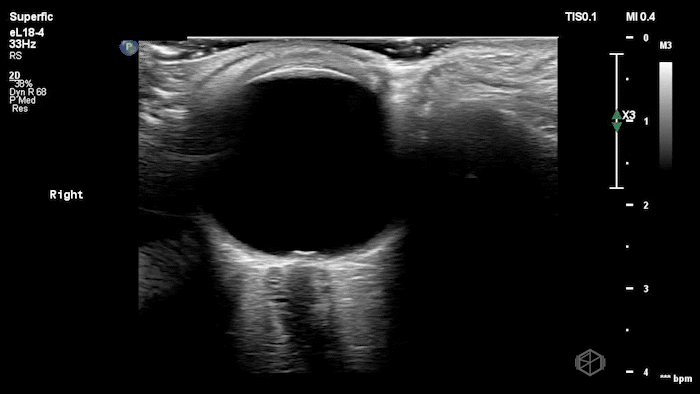

They were examining a 30’s female who was presenting to the ED with headaches for multiple years and had some vision disturbances. The performed an ocular POCUS that demonstrated the following:

The POCUS shows optic nerve edema right (0.793cm) greater than left (0.71cm) with bilateral papilledema. There may also be a faint vitreous detachment of the right eye. There was concerned for increased intracranial pressure.

ONSD measurements in this case are markedly abnormal. The optic nerve sheath diameter (ONSD) is measured 3 mm posterior to the globe. In adults, an ONSD > 5.0 mm is generally considered abnormal; values > 6.0 mm are strongly associated with raised intracranial pressure (ICP). Bilateral measurements of 7.9 mm (right) and 7.1 mm (left) are consistent with elevated ICP. The probe should be held lightly with ample gel to avoid artifactual compression (📚 PMID: 18509619, 18275454)

Point-of-care US measurement of optic disc elevation/height helps when fundoscopy is limited. Studies report cutoffs from ~0.6–1.0 mm: ≥1.0 mm is highly specific for papilledema in ED cohorts; lower cutoffs (≈0.6–0.7 mm) improve sensitivity. (📚 PMID: 24050798, 37227512)